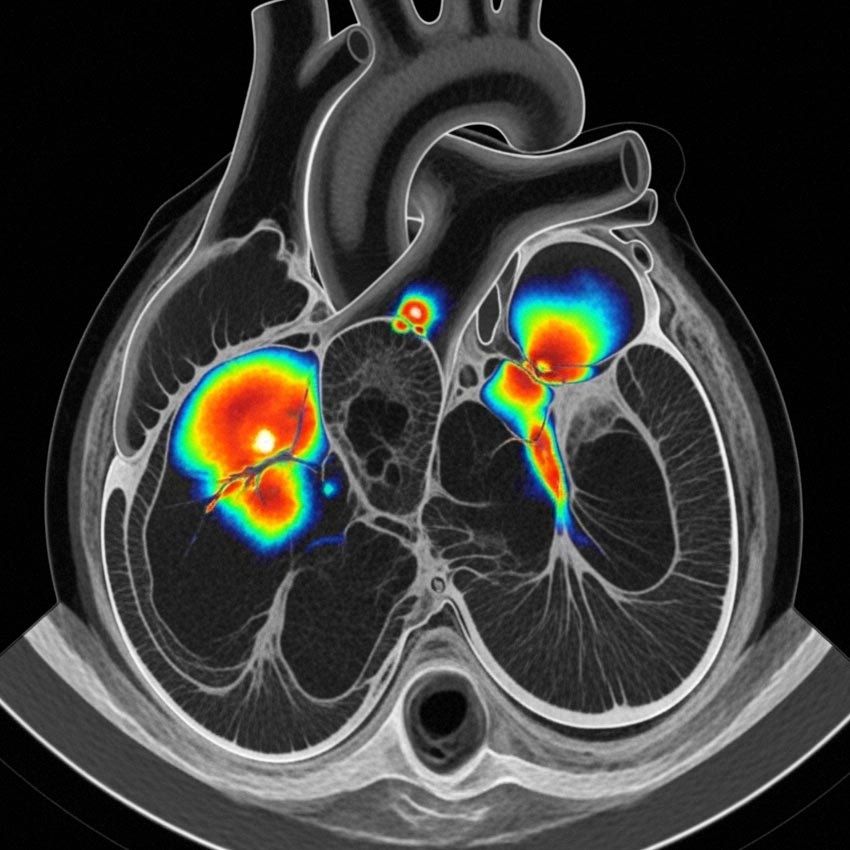

اسکن قلب

این روش پیشرفته برای بررسی جریان خون قلب، تشخیص گرفتگی عروق کرونر و ارزیابی عملکرد بطنها کاربرد دارد.

ما با استفاده از رادیوداروهای استاندارد و دستگاه گاما کمرا، تصاویری دقیق از فعالیت قلب شما تهیه میکنیم.

اسکن قلب در دو مرحله انجام میشود تا عملکرد قلب در شرایط مختلف بررسی گردد.